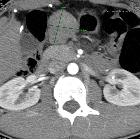

CT

Appearances vary with size and location. Typically the mass is of soft tissue density with central areas of lower density when necrosis is present (usually in larger tumors) that occasionally appear as fluid-fluid levels.

As the tumors are often exophytic, it can be difficult to delineate them on CT if the stomach is distended with barium, though the non-enhancing central necrotic area may be helpful. Deep crescent-shaped ulceration demonstrating an internal air-fluid level may be referred to as the Torricelli-Bernoulli sign .

Enhancement is typically peripheral (due to central necrosis) . Calcification is uncommon (3%) .

Metastases (distant, peritoneal, omental) or direct invasion into adjacent organs may be seen in more aggressive lesions. Lymph node enlargement is not a feature .

The diagnosis of malignant GIST requires histopathologic analysis, but certain characteristics suggest malignancy, which develops in 10-30% of these lesions. These include exogastric growth, diameter >5 cm, central necrosis, and extension to other organs.